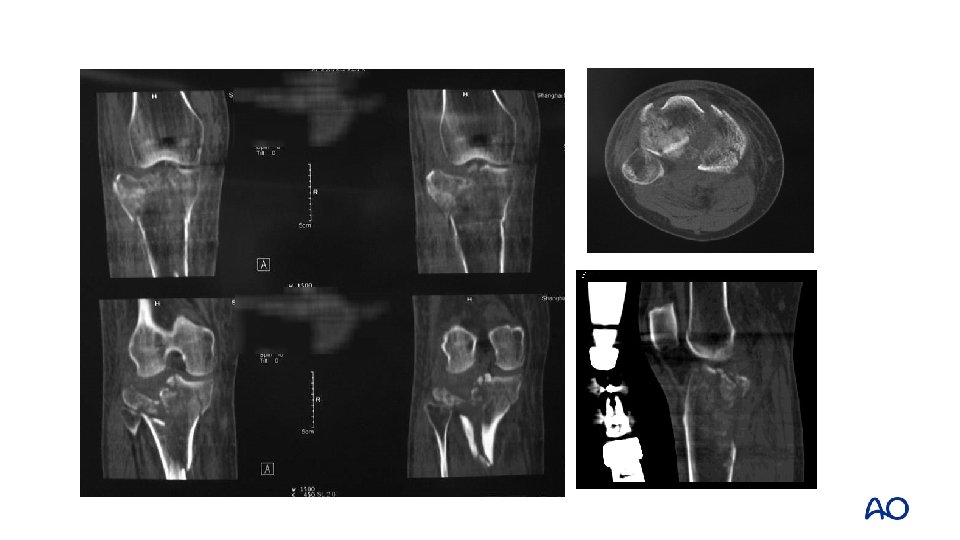

Schatzker type V, VI— 2 or 3 -column fracture Dual plating

3 -column fracture Flexion varus mechanism